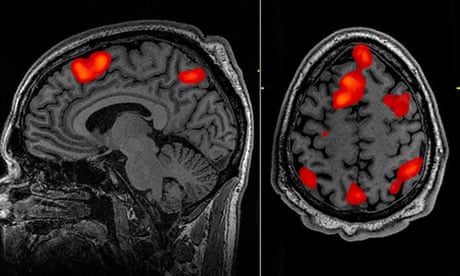

The learning process was intensive: three volunteers were required to lie in a scanner for 16 hours each, listening to podcasts. The decoder was trained to match brain activity to meaning using a large language model, GPT-1, a precursor to ChatGPT.

The participants were also asked to watch four short, silent videos while in the scanner, and the decoder was able to use their brain activity to accurately describe some of the content, the paper in Nature Neuroscience reported.